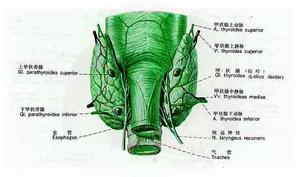

甲狀旁腺

甲狀旁腺

甲狀旁腺

甲狀旁腺